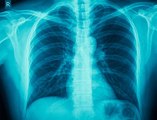

This Day in History: , German Scientist Discovers X-Rays .<br />November 8, 1895.<br />Wilhelm Conrad Rontgen's , discovery of X-rays happened accidentally as he conducted a test on cathode rays.<br />He noticed a glow on a screen <br />coated with chemicals. <br />Rontgen called the rays <br />that caused the glow X-rays.<br />After conducting more experiments, Rontgen discovered that X-rays could pass through human flesh, but not harder substances such as bone.<br />He also learned that they could <br />be photographed. The discovery <br />was hailed as a medical miracle.<br />X-rays were first used on a <br />battlefield during the Balkan War in 1897.<br />Rontgen received the Nobel Prize in physics for his work but never attempted to gain financially for his discovery